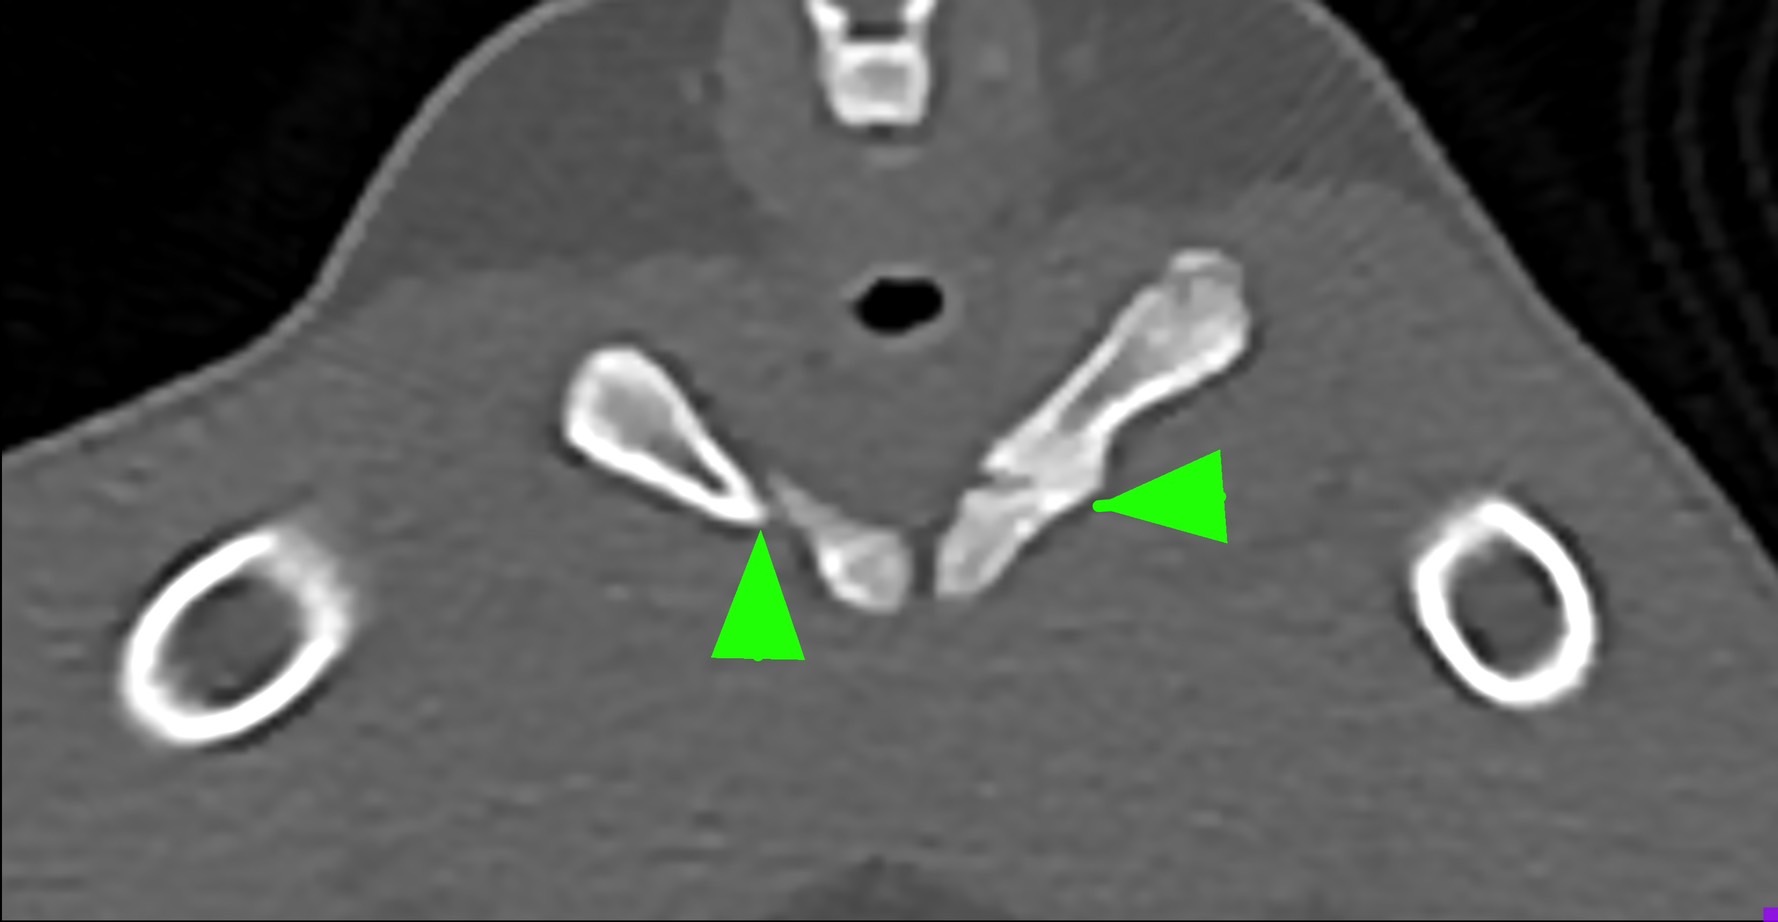

狗狗後腳癱瘓也有可能是血栓 不一定是骨骼神經肌肉問題喔

後肢癱瘓的柴柴經由他院轉診來築心做電腦斷層掃瞄因為狗狗以前病史有椎間盤突出問題

所以以為是脊椎問題想要來評估手術

掃瞄結果診斷為動脈血栓造成

主動脈血栓栓塞是一種急性且危及生命的疾病,當血液凝塊從心臟或其他部位脫落,經過血液循環流向並卡住動脈中的某些血管,造成局部的血液供應中斷、相應部位的器官或組織缺氧,將引起疼痛、損傷甚至壞死。

此患犬在電腦斷層影像以及後續追蹤的超音波下都可見明顯血栓影像